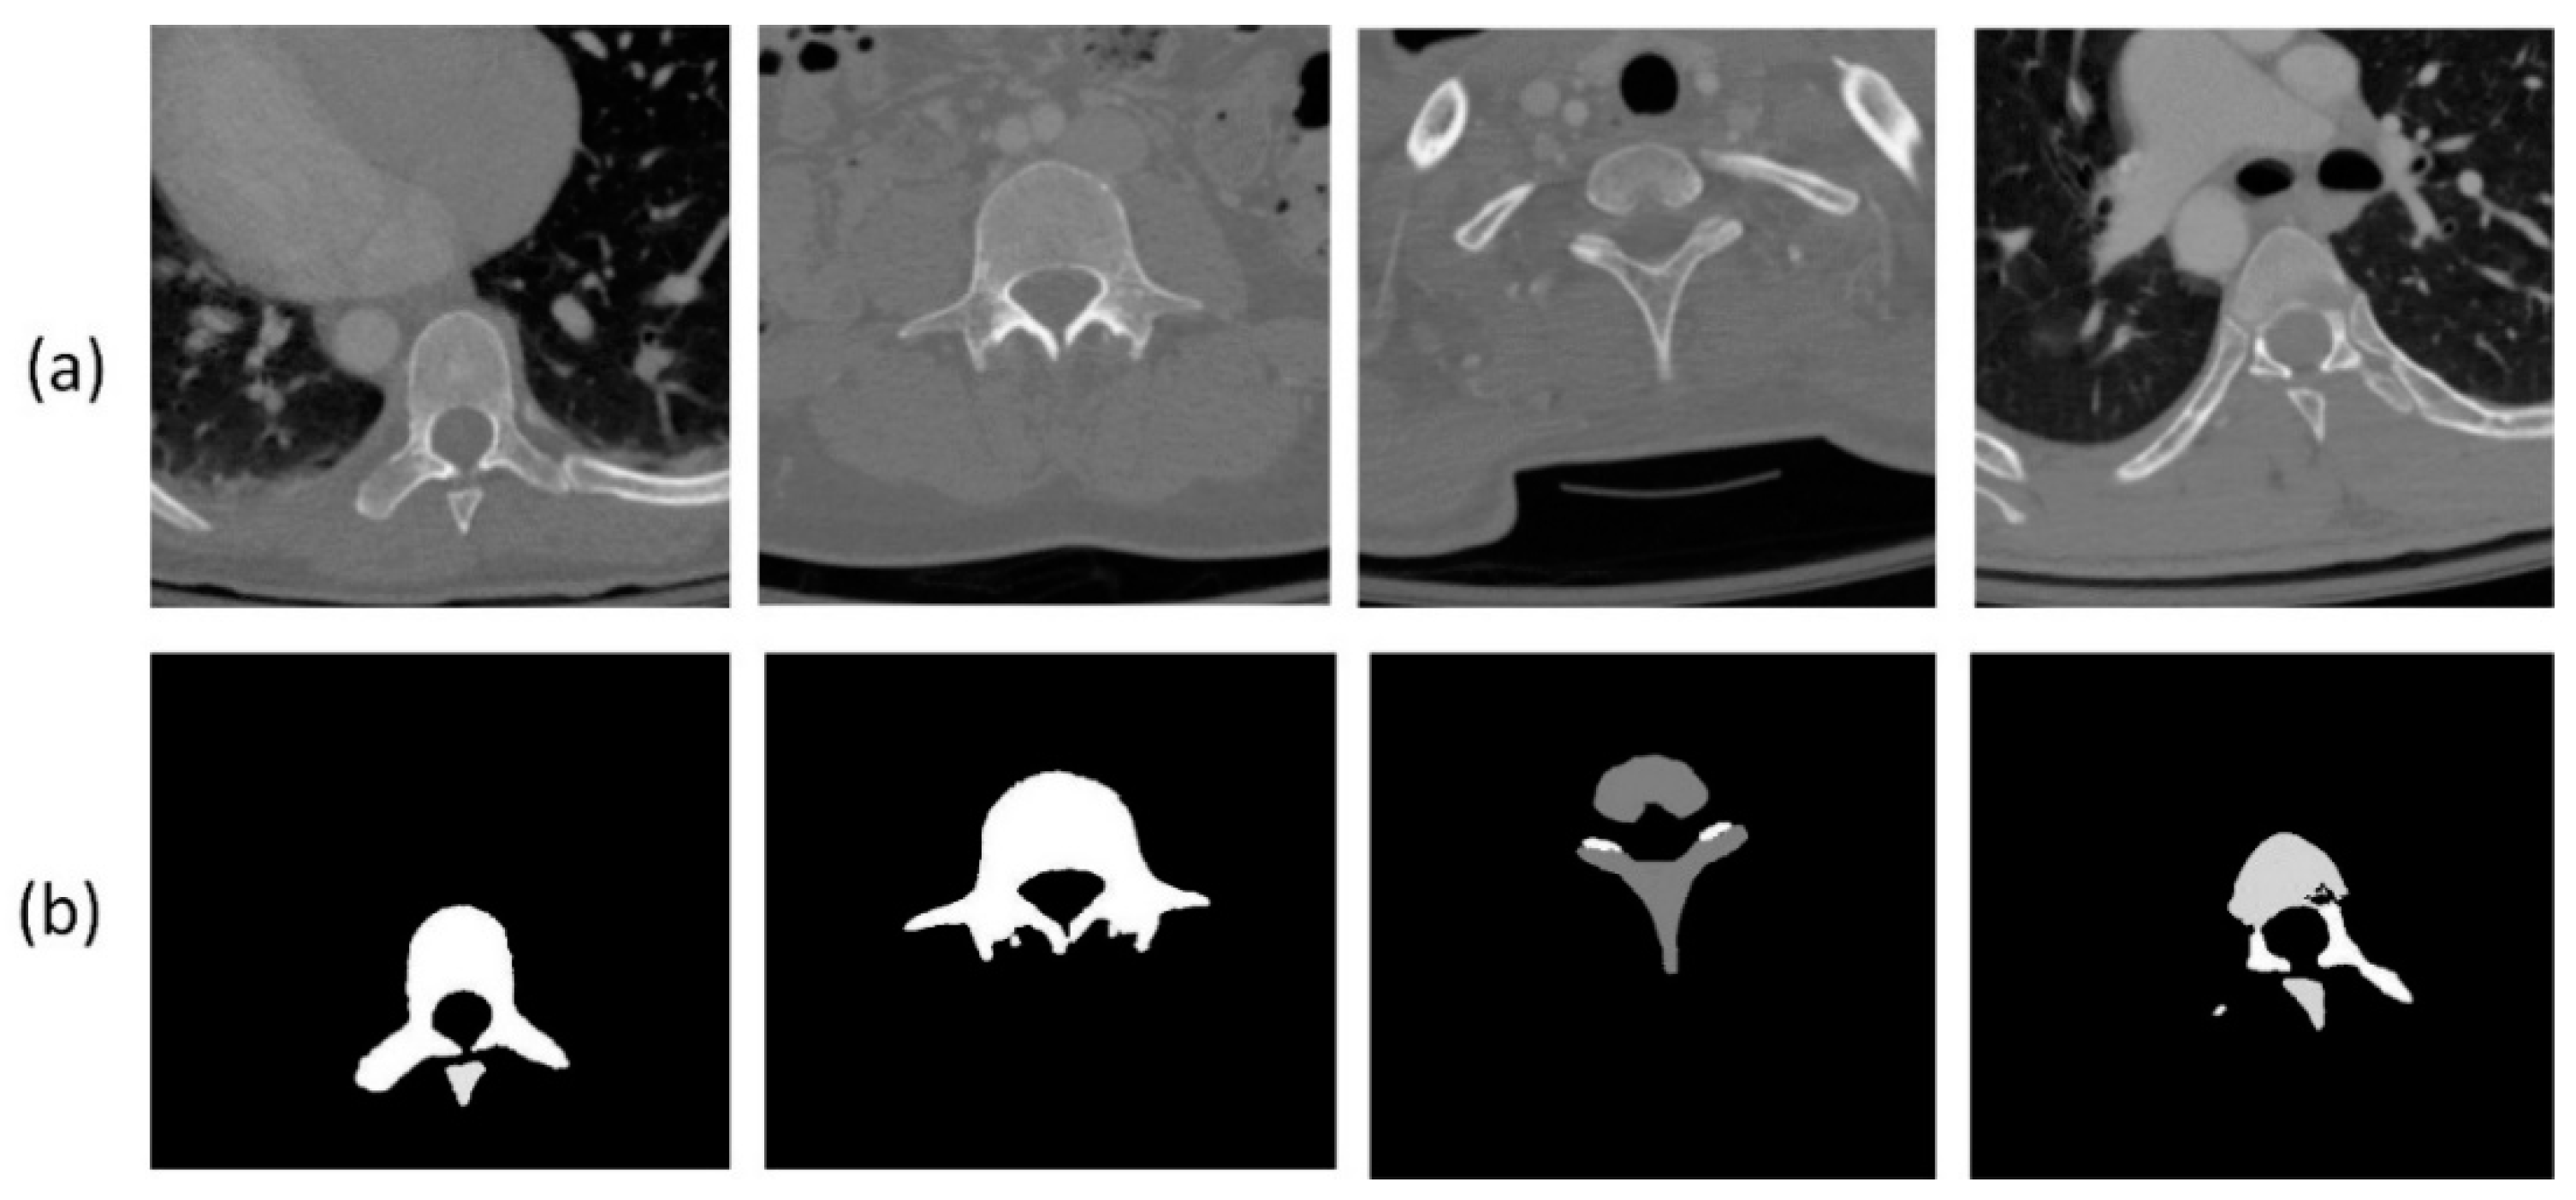

2.1. Preprocessing